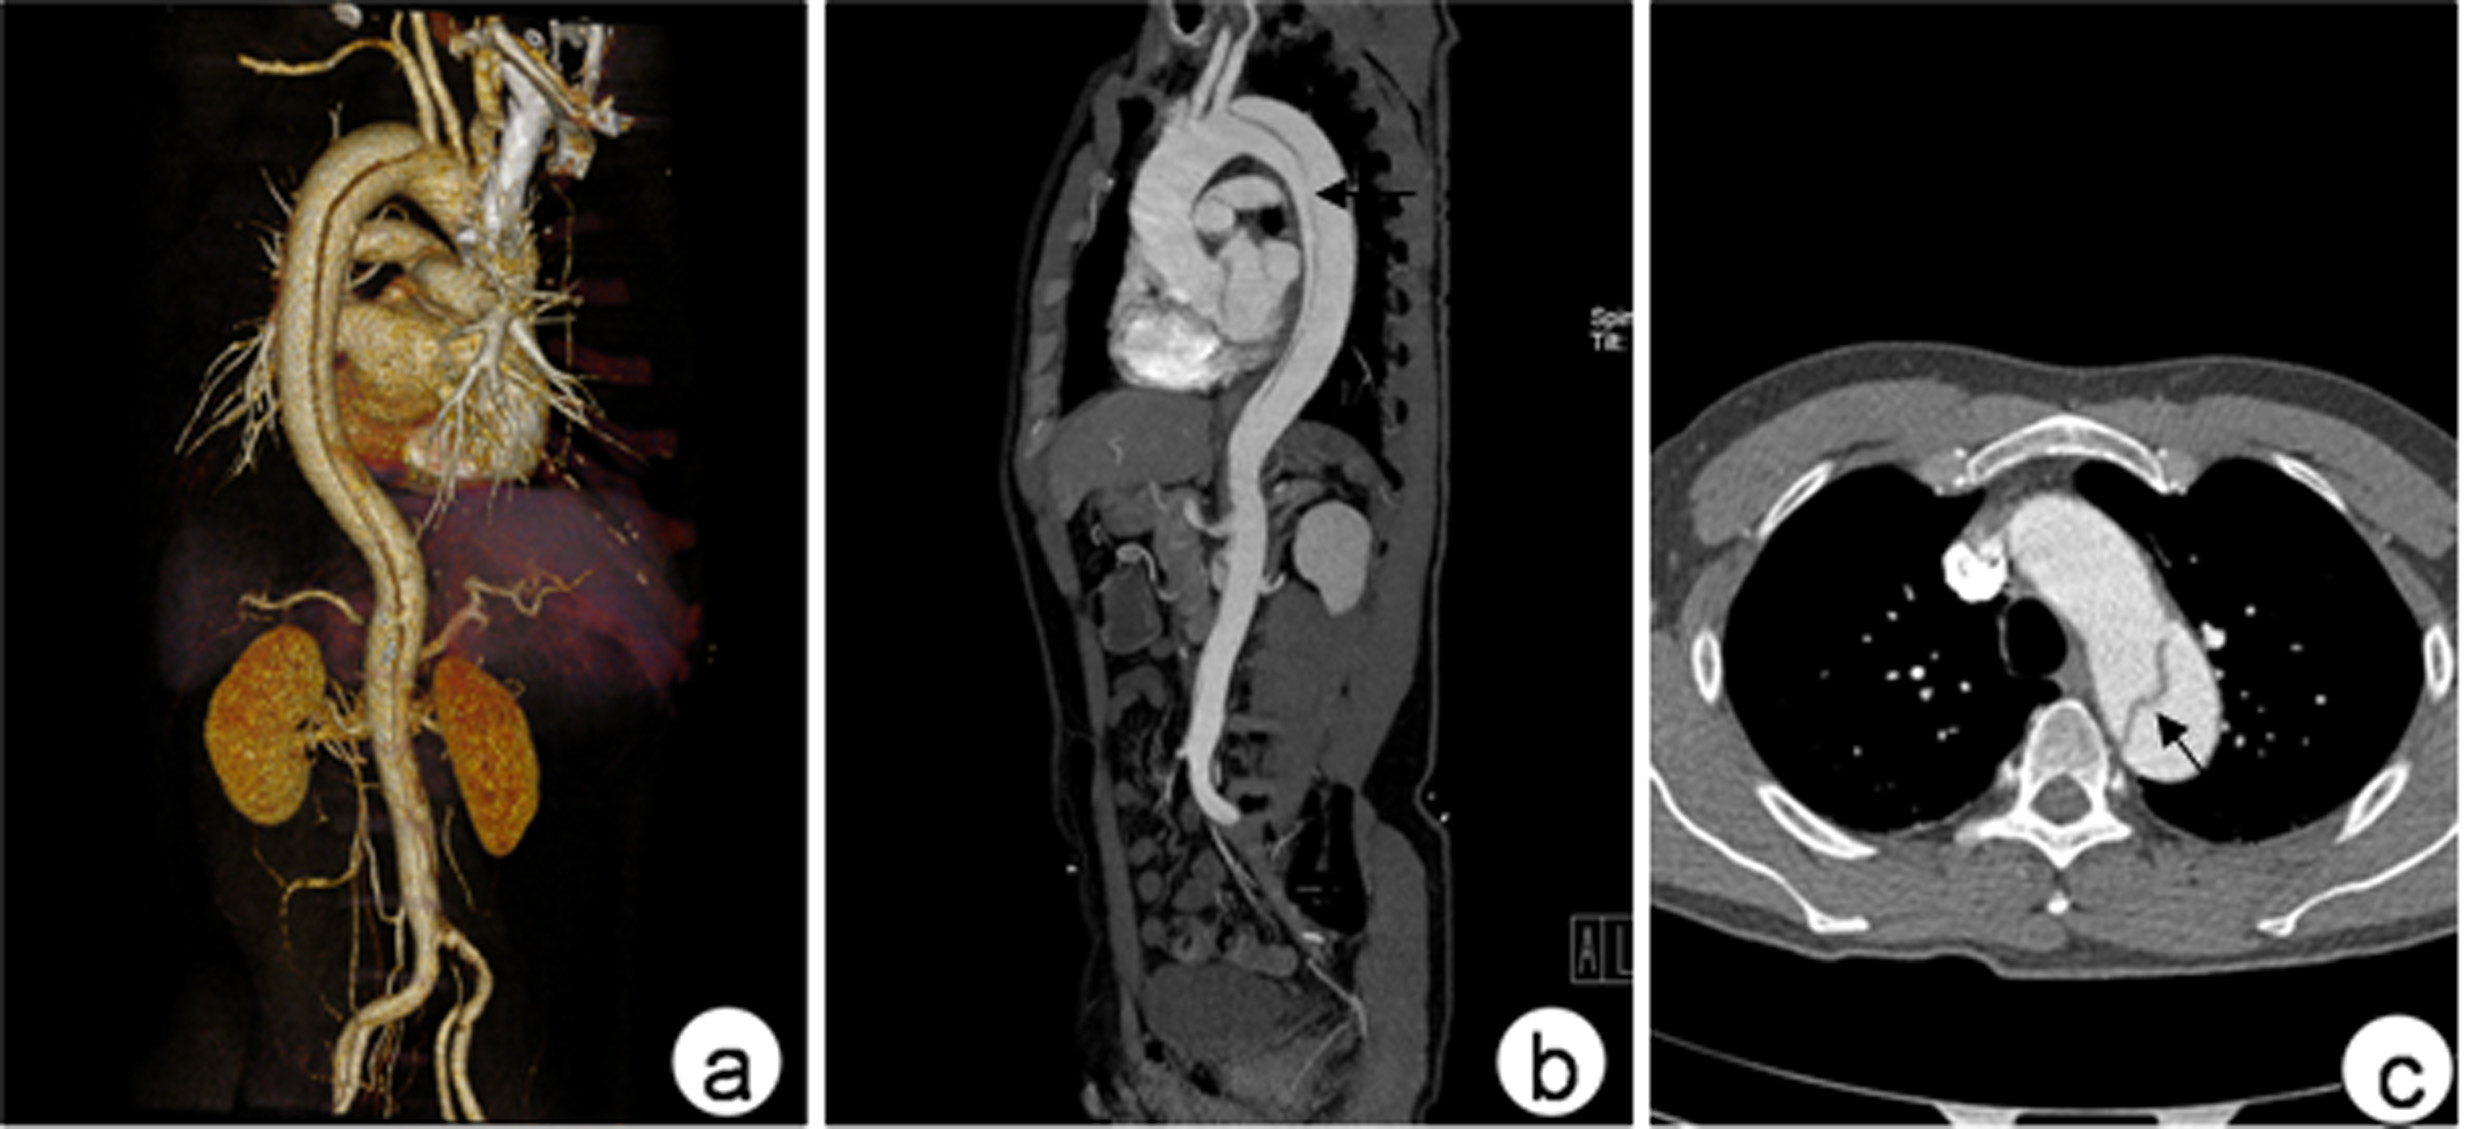

外科开放手术主动脉夹层患者开放手术治疗目前主要用于standford A 型病人,但截瘫发生率可高达5%~40%,其死亡率与内科药物治疗无明显差异。随着人工血管的不断发展,国内孙立忠等首次使用支架“象鼻”术治疗Stanford A 型主动脉夹层,此手术方式的优点是覆盖了夹层内膜破口,扩大真腔,缩小假腔,增加血供。 腔内修复治疗1998 年,Dake 等首先采用腔内修复治疗Standford B 型夹层,此后得到不断发展及改进,从近十年的治疗结果来看,腔内治疗Standford B 型主动脉夹层安全有效,创伤小。

腔内修复治疗指针目前多数常采用的是Nienaber提出的修复指针:(1)近端破口与左锁骨下动脉开口距离>10~15mm;(2)假腔不断扩大;(3)形成夹层动脉瘤, 直径>55cm;(4)内膜破口持续存在;(5)疼痛无法缓解;(6)肠系膜上动脉及至少一侧肾动脉由真腔供血;(7)至少有一侧髂股动脉无夹层分离。

腔内修复治疗的时机选择夹层急性期由于主动脉壁会发生水肿,内膜脆弱,腔内修复术后会增加夹层内膜撕裂及主动脉破裂的发生率,但早期腔内修复有利于夹层真假腔的重构,因此Kato 等[10]提出应宜在发病4w 后、慢性期之前行腔内修复治疗,急性期应在发病3w 后给予腔内修复治疗,但对于有胸腔积液、疼痛无法缓解、主动脉分支血管缺血无法缓解及降主动脉直径>4.5cm者应急诊行腔内修复治疗, 以免在等待过程中发生夹层破裂及其他致命性并发症。